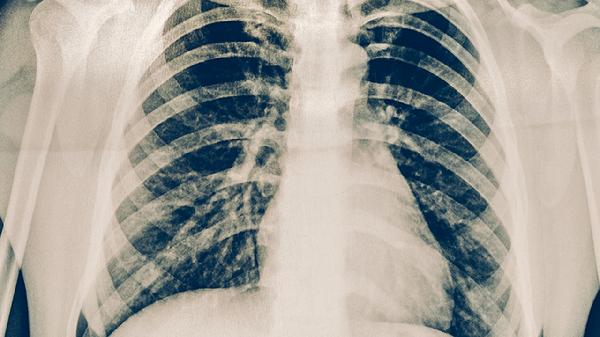

結(jié)核分枝桿菌進(jìn)入人體后可能處于潛伏狀態(tài),未引起明顯免疫反應(yīng)。這類感染者結(jié)核菌素試驗(yàn)或干擾素釋放試驗(yàn)呈陽性,但胸部影像學(xué)檢查無活動(dòng)性病灶。潛伏感染者無須特殊治療,但需定期復(fù)查,避免免疫力下降時(shí)發(fā)展為活動(dòng)性肺結(jié)核。

當(dāng)結(jié)核病灶局限于肺尖或胸膜等非敏感區(qū)域時(shí),可能不刺激咳嗽反射或胸膜神經(jīng)。這類患者常在體檢時(shí)通過胸部X線發(fā)現(xiàn)鈣化灶或纖維條索影。病灶穩(wěn)定者無須治療,但需監(jiān)測(cè)病灶變化。